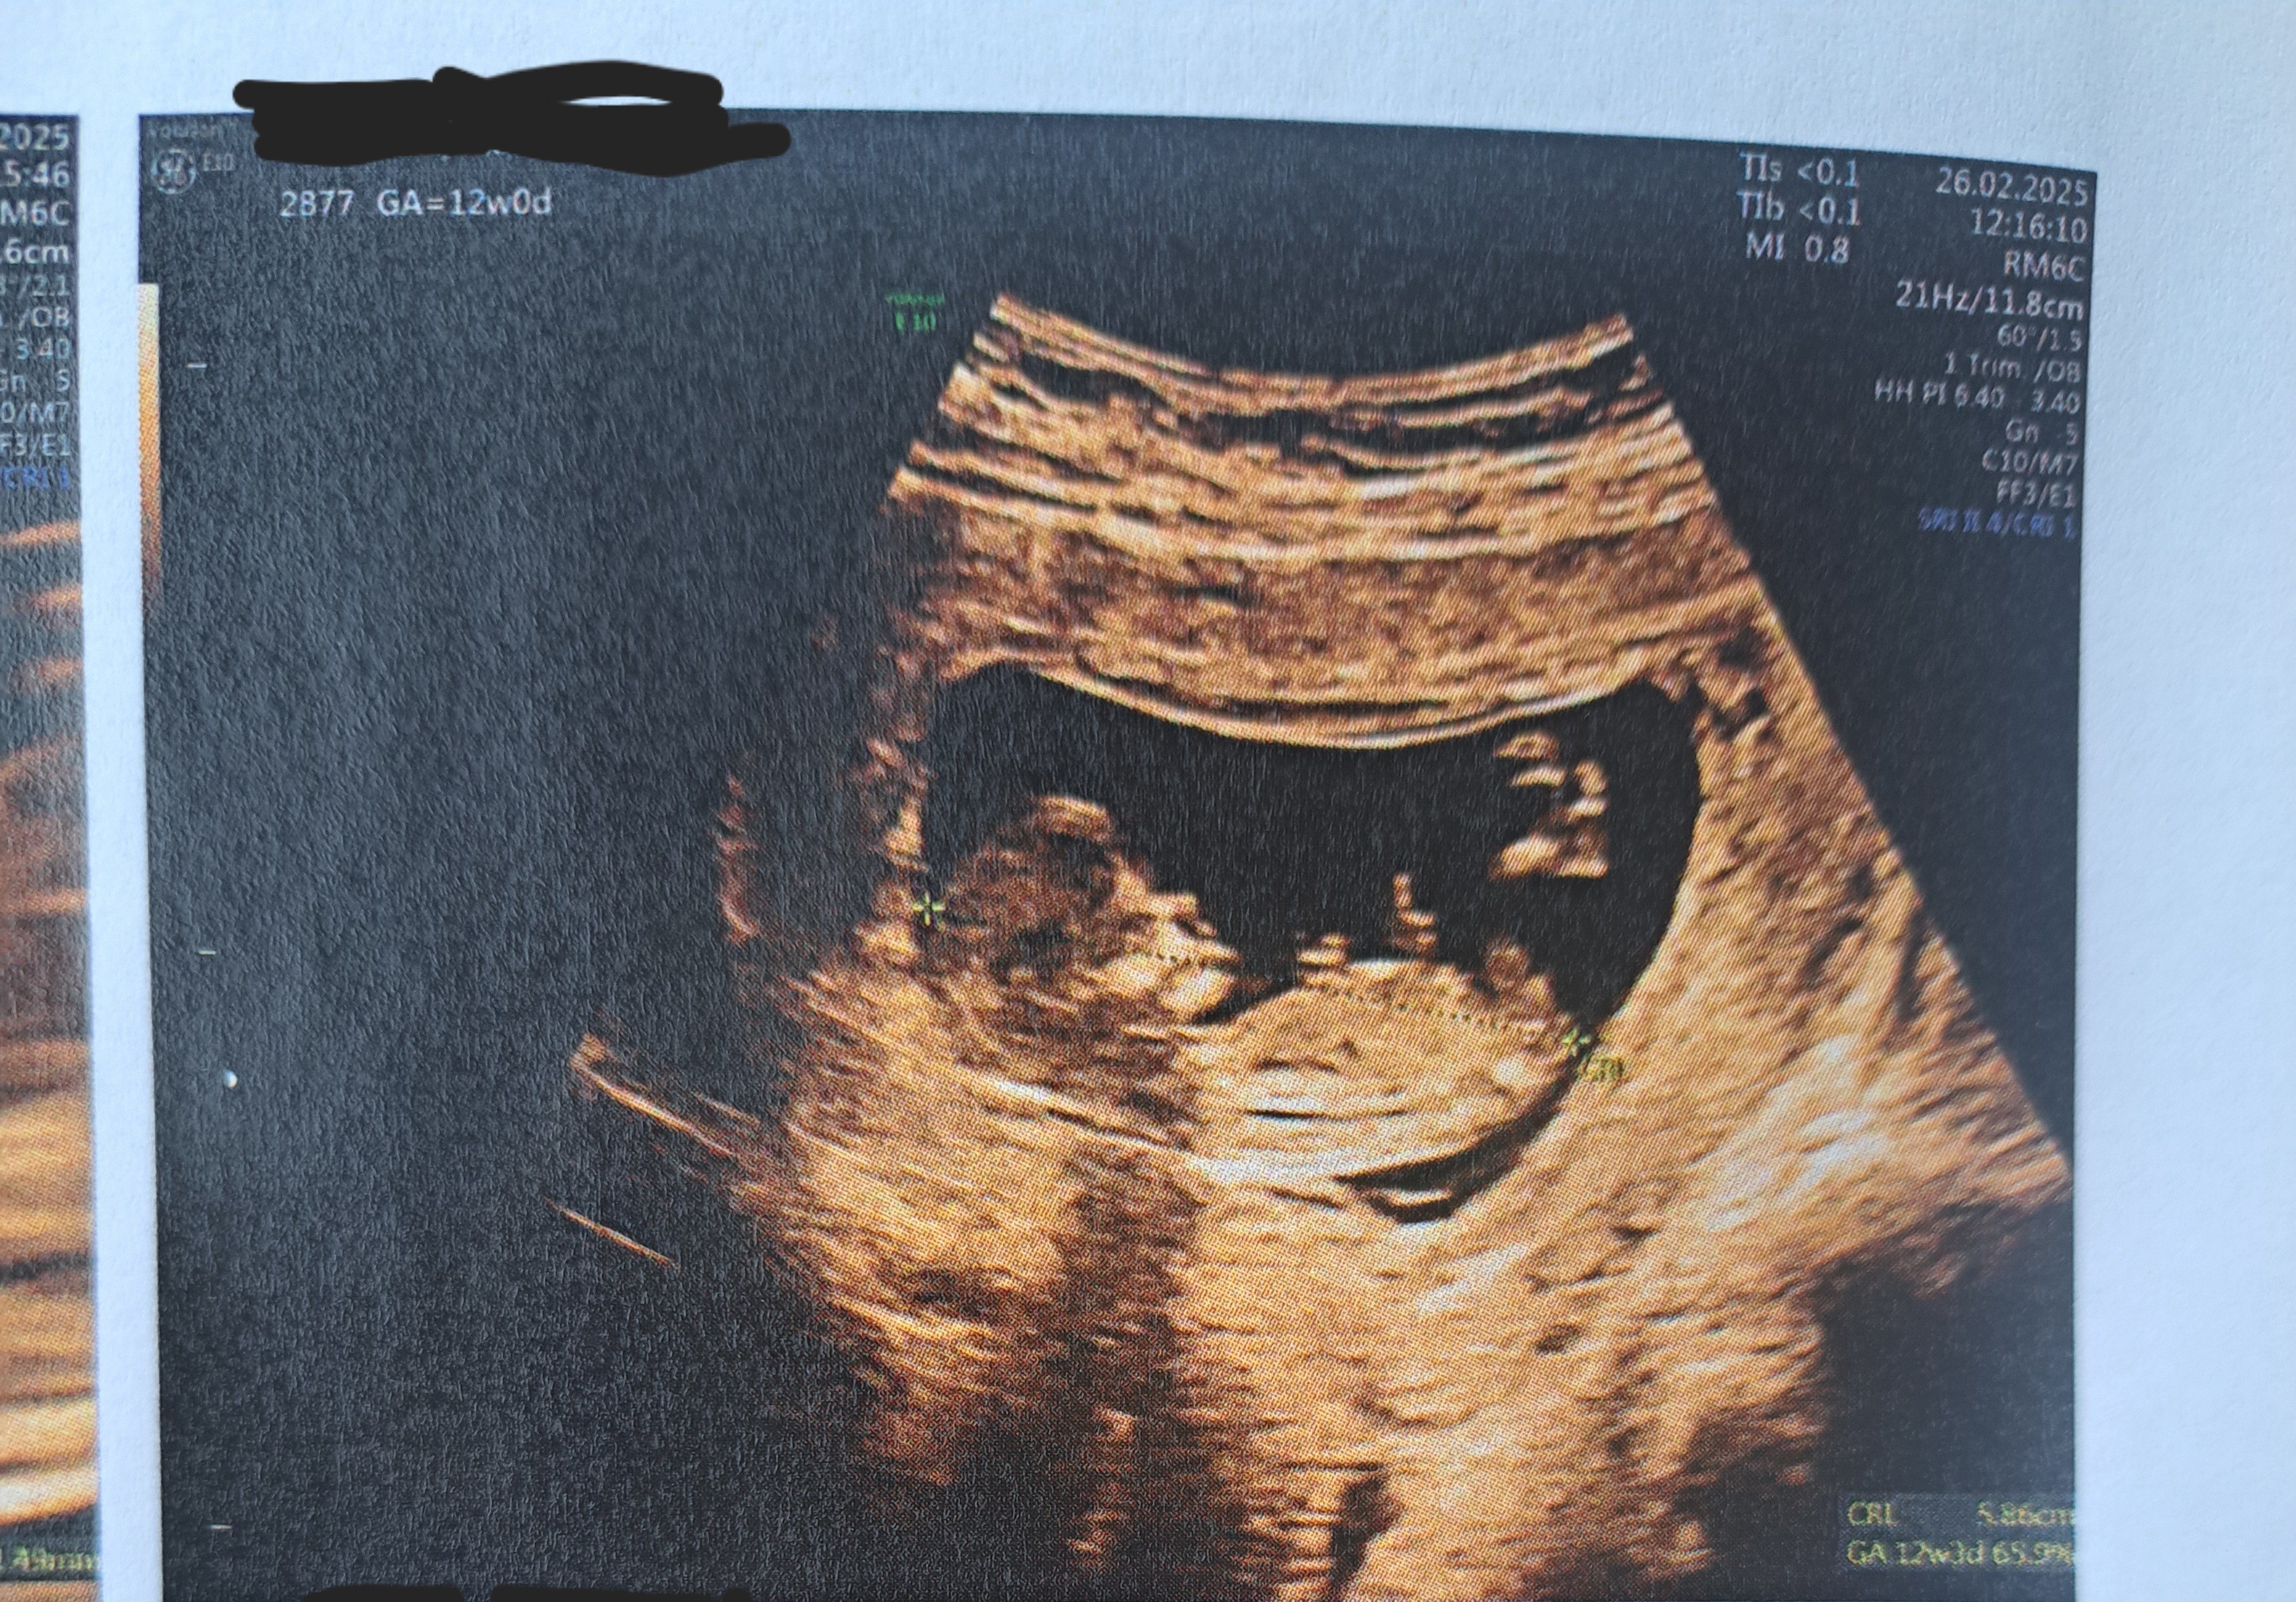

Cześć,

jestem po I prenatalnym. Lekarz rzeczowy, ale tak szybko skończył, że nie zdążyłam się zapytać czy coś widzi 🫣 Jakieś propozycje?

• 20250226_122620.jpg

20250226_122620.jpg

2,2 MB · Wyświetleń: 250